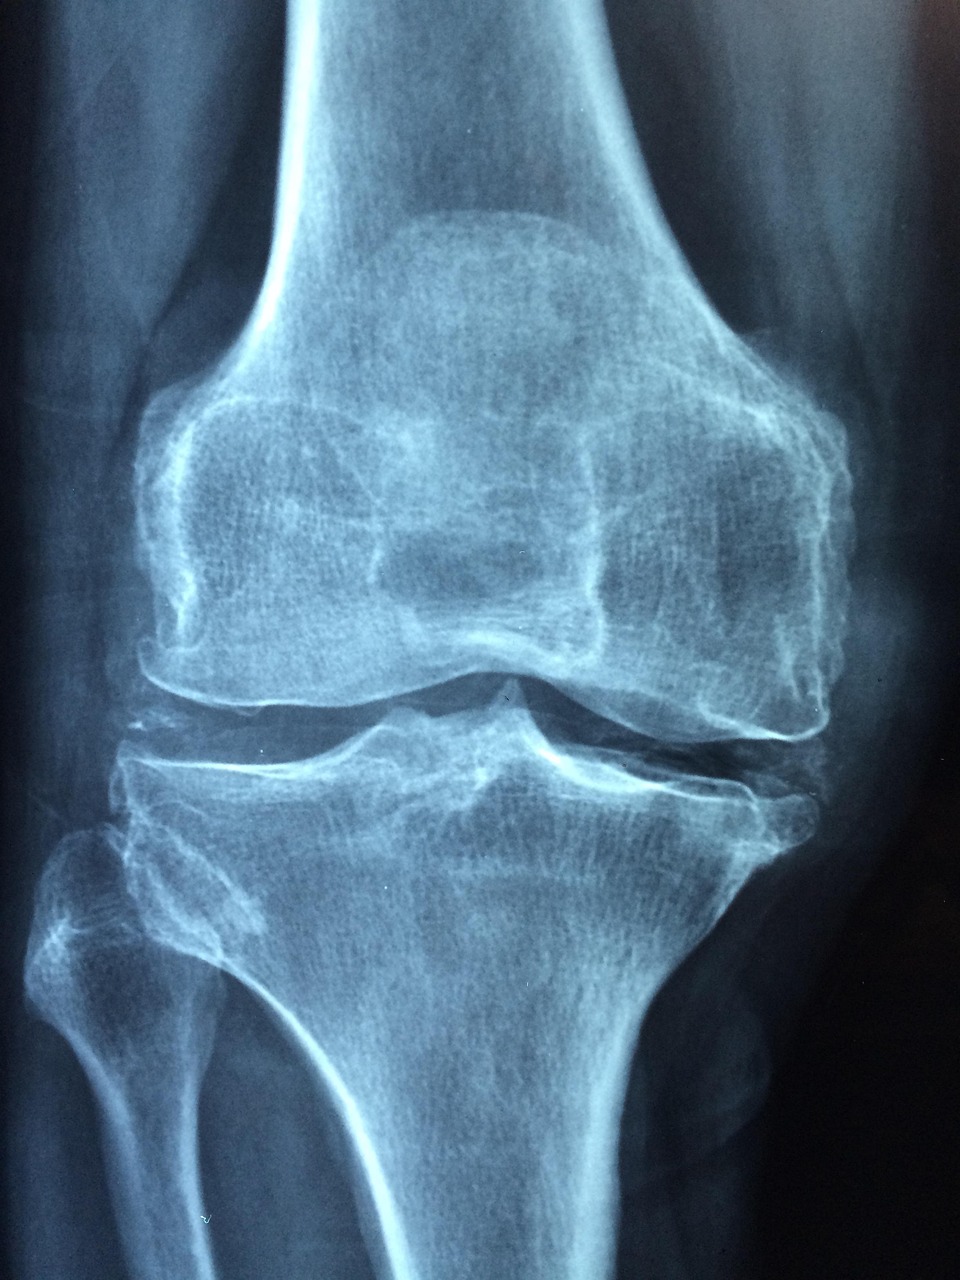

1. 골다공증이란 무엇인가?

골다공증은 뼈의 강도가 약해져 작은 충격에도 골절이 쉽게 일어나는 만성 질환입니다. 뼈의 내부가 구멍이 숭숭 뚫린 듯한 상태가 되어, 넘어지거나 가벼운 충격에도 손목, 척추, 대퇴골 골절이 발생할 수 있습니다.

5. 검사 방법 (DXA·QUS)

| DXA (이중에너지 X선 흡수계측법) | 요추·대퇴골 촬영 | 정확도 최고, 국제 표준 | 방사선 노출, 비용↑ |